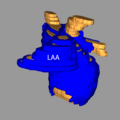

- Carma norm LAA.png 591 × 591; 98 KB

- Carma vert LAA.png 579 × 626; 148 KB